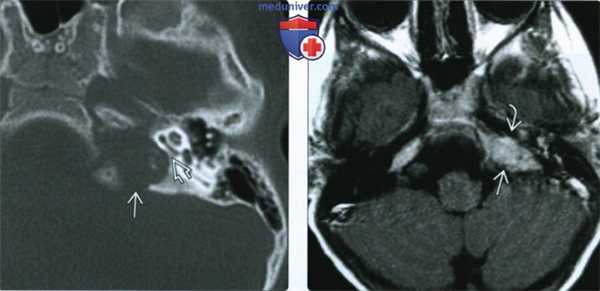

(Слева) МРТ, Т1-ВИ, сагиттальный срез: у семилетней девочки с центральным несахарным диабетом в структуре гипоталамуса визуализируется мягкотканное объемное образование. Обратите внимание на отсутствие нормального очага укорочения Т1 в гипофизе (задней доли), что часто обнаруживается у детей с несахарным диабетом.

(Справа) МРТ, постконтрастное Т1-ВИ, режим подавления сигнала от жира, корональный срез: у этого же ребенка отмечается контрастное усиление узлового образования гипоталамуса. Утолщение стебля гипофиза является наиболее частым признаком вовлечения в процесс ЦНС при гистиоцитозе из клеток Лангерганса (ГКЛ)..

(Слева) При КТ в аксиальной проекции определяется объемное образование верхушки пирамиды левой височной кости, вызывающее фестончатость ушной капсулы (ЛКГ). Передний край объемного образования прилежит к каменистому сегменту внутренней сонной артерии.

(Справа) При МРТ Т1 с КУ в аксиальной проекции у этого же пациента с ЛКГ наблюдается однородное контрастирование объемного образования верхушки пирамиды височной кости. Видно, что к объемному образованию прилегает каменистый сегмент внутренней сонной артерии.